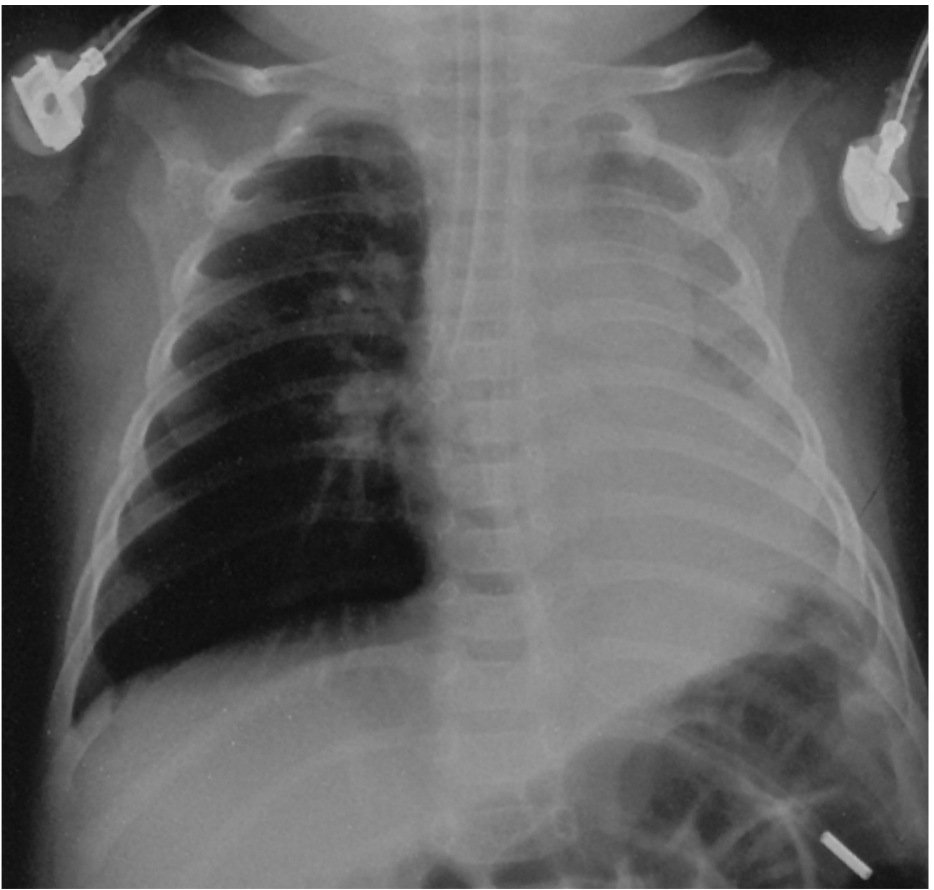

A 5 year old male presents to ED after an episode of near drowning. He is intubated on arrival and the Xray below is taken soon after intubation.

A CXR is taken.

a. State four (4) abnormal findings in this CXR. (4 marks)

His weight is 20 kg.

b. List the initial ventilator settings that you would commence. (5 marks)

45 minutes after instituting these settings, his Peak Inspiratory pressures are 50 cm H20.

c. State four (4) steps that you would perform to rectify this problem. (4 marks)